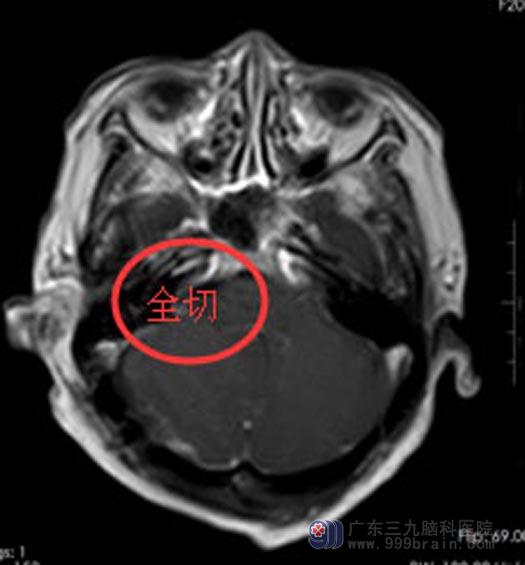

在广东三九脑科医院综合神经外科,袁阿姨及家属充分了解病情后,同意手术治疗。由鲁明副院长主刀在全麻下行“右侧桥小脑角占位切除术”,手术顺利,术中出血仅100ml。病理检验报告:病变符合(右侧桥小脑角)良性病变,结合临床及影像,考虑蛛网膜囊肿可能性大。

术后的袁阿姨神清语明,可以自主下地活动,无恶心呕吐、头晕头痛等不适,也没有出现声音嘶哑等后遗症,欢欢喜喜地出院了。